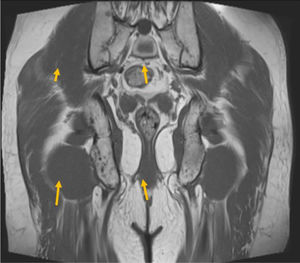

La resonancia magnética (RM) define mejor las características lesionales. Generalmente, se observan lesiones hipointensas no expansivas homogéneas en el tejido endomedular. En la RM abdomino-pélvica realizada posteriormente para ampliar estudio, la paciente presentó lesiones de baja intensidad de señal en secuencias potenciadas en T1 y T2 (hueso denso maduro), que no restringían el movimiento browniano a la libre difusión de las partículas de agua (figura 2). No captaban ningún tipo de contraste (gadolinio ni yodo) en la RM ni en los estudios funcionales de Medicina Nuclear, como gammagrafía ósea y PET-TC. Por dichas características y dada la estabilidad radiológica, se descarta el diagnóstico de metástasis óseas, corroborando la naturaleza benigna de dicho proceso. Se evalúa como diagnóstico diferencial el que se trate de una enostosis múltiple dentro del amplio espectro de enfermedades que plantean las displasias osteoesclerosas, con alta probabilidad de que se trate de una osteopoiquilosis4. Figuras 3 y 4.